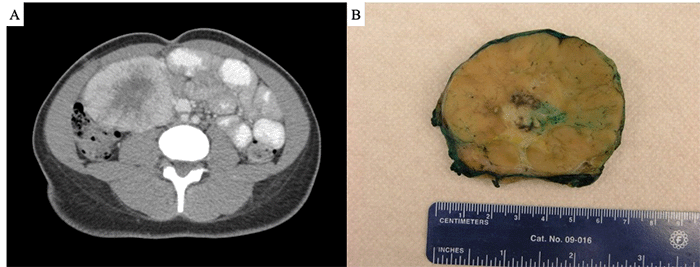

Two months after the onset of abdominal pain, she presented to our emergency department with periorbital and bilateral lower extremity edema, electrolyte abnormalities, mild transaminitis, hypoalbuminemia, and hypertension. Intermittent right-sided abdominal pain persisted. Repeat CT showed interval mass growth to 9.5 × 9.0 × 7.3 cm, with associated bilateral hydronephrosis despite normal renal function (Figure 1A). The mass was adjacent to the duodenum and inferior vena cava (IVC) posteromedially, the small bowel medially, the right colon inferolaterally, and the abdominal wall anteriorly, with well-defined circumferential fat planes. It was associated with the small bowel and right colon mesentery but appeared to have a separate blood supply. No other lymphadenopathy or abnormalities were noted. Workup for a functional neuroendocrine tumor and pheochromocytoma was negative. Electrolytes and transaminitis normalized with medical management of her hypertension. Percutaneous ultrasound-guided core needle biopsy was performed, revealing abnormal lymphoid tissue with increased vascular stroma surrounding regressed follicles, without evidence of lymphoma, suggestive of hyaline vascular type Castleman disease. The patient opted for surgical excision.

Figure 1. Imaging and Gross Pathology. Published with Permission

(A) CT scan demonstrating a large mass at the confluence of the small bowel and right colon mesentery. (B) Gross pathology of a well-circumscribed 8.8 × 7.8 × 5.9 cm mass.

Laparoscopic exploration revealed a large, non-invasive mass within the ileocolic mesentery, exerting mass effect on the retroperitoneum. Preoperatively placed ureteral stents confirmed the ureters were uninvolved. The mass extended medially to the small bowel mesentery root and laterally to the cecum, consistent with preoperative imaging. Due to limited laparoscopic exposure and relative fixation of the mass, a midline laparotomy was performed, and a wound protector was placed to facilitate evisceration. The mass was carefully dissected from the superior mesenteric artery (SMA), ileocolic vessels, and marginal artery, preserving bowel perfusion. The resulting mesenteric defect was closed, and fiducials were placed along the suture line. Blood loss was minimal, and the patient’s postoperative recovery was uneventful, leading to discharge on postoperative day four.

Final pathology revealed an 8.8 × 7.8 × 5.9 cm mass (Figure 1B) characterized by regressively transformed, atretic follicles, “onion-skinning” of mantle zones, and hypervascularity, including vessels penetrating follicles at right angles (Figure 2). Extrafollicular areas exhibited fibrosis, SMA-positive spindled cells, increased plasma cells, myxoid change, and focal necrosis (Figure 3A). ALK1 staining was positive in the spindled areas and a subset of non-lymphoid follicular cells (Figure 3B and C). Fluorescence in situ hybridization (FISH) analysis confirmed an ALK rearrangement (Figure 3D).